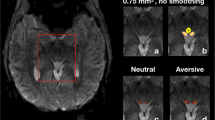

Functional magnetic resonance imaging (fMRI) has become an essential tool for studying human brain function. Here we describe the application of this technique to anesthetized monkeys. We present spatially resolved functional images of the monkey cortex based on blood oxygenation level dependent (BOLD) contrast. Checkerboard patterns or pictures of primates were used to study stimulus-induced activation of the visual cortex, in a 4.7-Tesla magnetic field, using optimized multi-slice, gradient-recalled, echo-planar imaging (EPI) sequences to image the entire brain. Under our anesthesia protocol, visual stimulation yielded robust, reproducible, focal activation of the lateral geniculate nucleus (LGN), the primary visual area (V1) and a number of extrastriate visual areas, including areas in the superior temporal sulcus. Similar responses were obtained in alert, behaving monkeys performing a discrimination task.